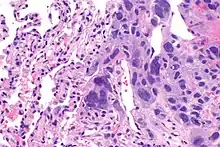

A micrograph view of dysgerminoma, showing actively dividing lobulated nuclei.[4]

Dysgerminomas are comparable to testicular seminomas and account for approximately 32- 37% of all OGCTs.[1] They are particularly prominent in individuals with dysgenic gonads of 46, XY pure gonadal dysgenesis patients.[1] Based on gross examinations, dysgerminomas are characterized by having a ‘solid, lobulated, tan, flesh-like gross appearance with a smooth surface'.[1] Microscopically, the cellular structure is distinguished by a round-ovoid shape containing ample eosinophilic cytoplasm and an irregularly shaped nuclei.[1] The uniformly positioned cells are separated through the fibrous strands and lymphocytic infiltration is commonly observed.[5]